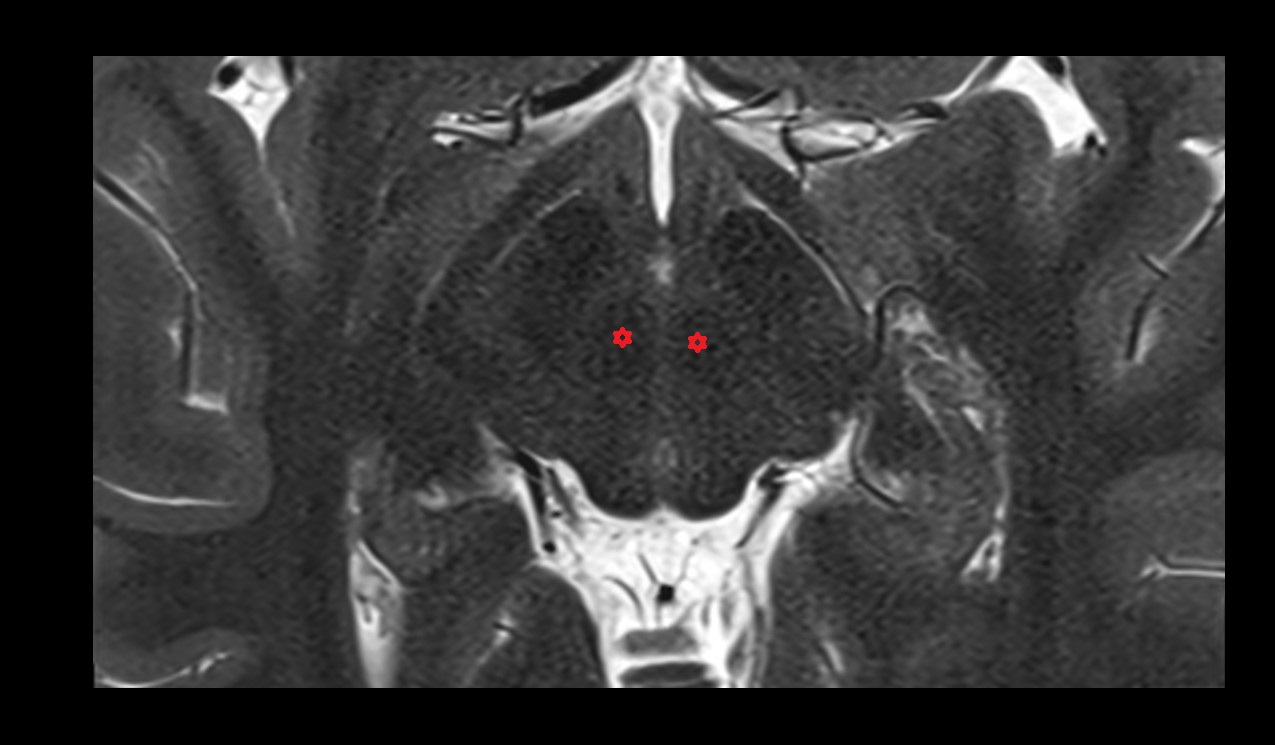

- Cornu Ammonis 1 (CA1)

- Cornu ammonis 2 (CA2)

- Cornu ammonis 3 (CA3)

- Cornu ammonis 4 (CA4)

- Cornu ammonis

- Body of hippocampus

- Head of hippocampus

- Tail of hippocampus

- Hippocampus